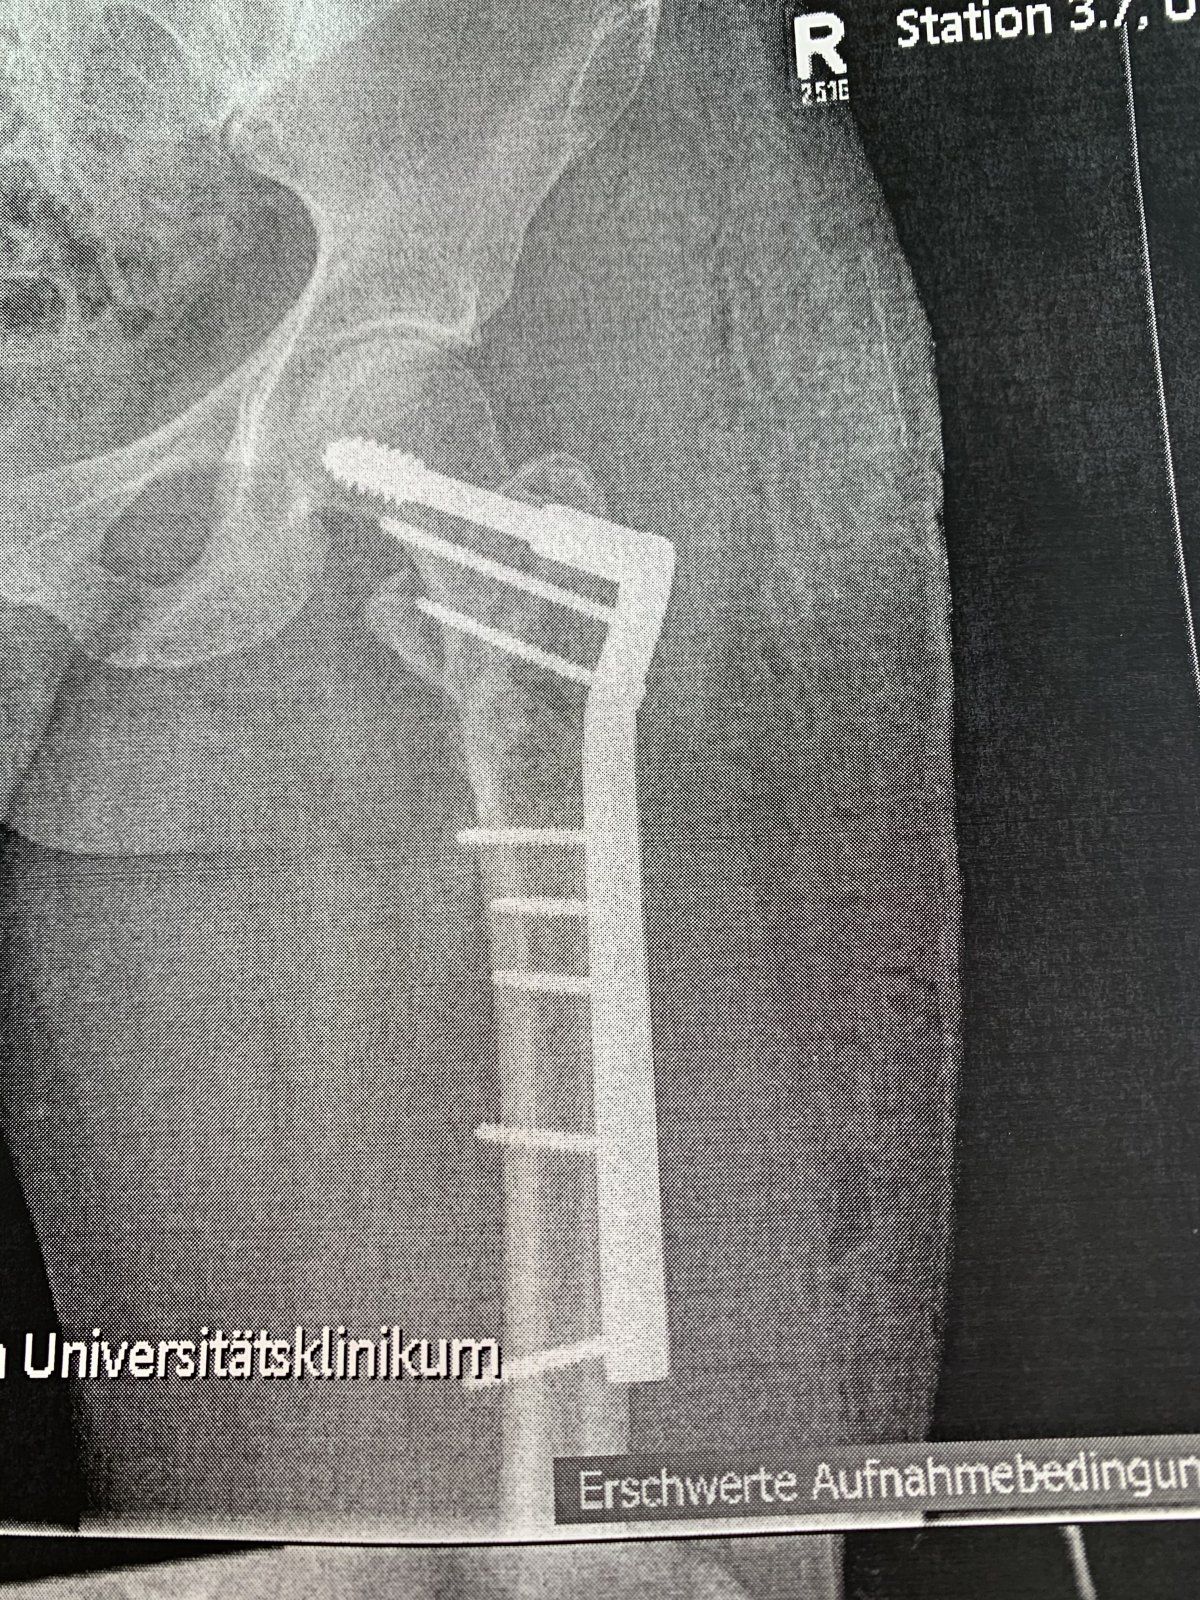

Ich habe die Entfernung der Dhs in einer Tagesklinik mit Vollnarkose machen lassen. Die Op hat etwas über 2 Stunden gedauert, weil es aber zu einem Problem gekommen war - es fehlte im Werkzeug ein bestimmter Schraubenzieher, so dass der Operateur beinahe das grösste Teil nicht herausbekommen hätte. Das hätte ich nun wirklich nicht unter Spinal Betäubung mitkriegen wollen...